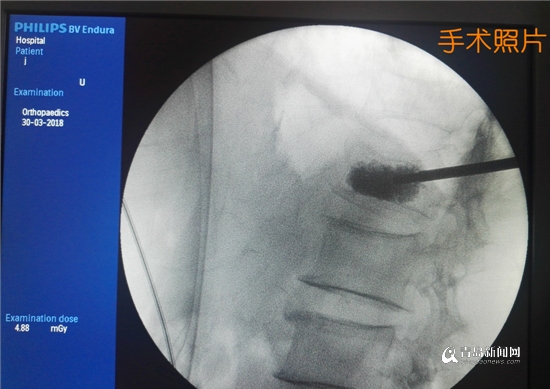

經(jīng)過積極準備,趙明偉為矯大爺在局部麻醉下實施了微創(chuàng)手術(shù),30分鐘后手術(shù)順利完成,4小時后老人已經(jīng)可以下床走路,腰部疼痛完全消失。3天后,老人康復出院。

椎體成形術(shù)手術(shù)照片

“椎體成形術(shù)的原理是在X光機的精準定位下,通過2mm小針孔將骨水泥精確注入骨折部位,以達到增加病變椎體強度穩(wěn)定骨折,防止椎體進一步塌陷,緩解疼痛的目的”,趙明偉介紹說,“這個過程就像‘打針’一樣,創(chuàng)傷小、安全性高、鎮(zhèn)痛速度快,解除了患者劇烈疼痛和長期臥床的困擾?!?/p>